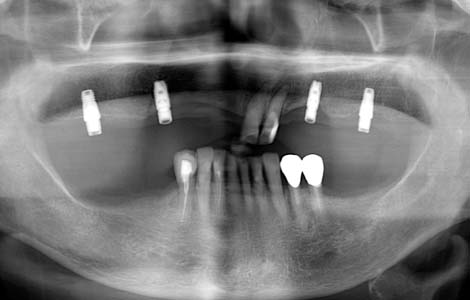

審美性も良くなる

写真の症例は上顎に4本のインプラントを固定源とした入れ歯です。通常の入れ歯に比べ噛んだときの感触が非常によく、歯かけるバネがなく見た目も優ています。インプラントがしっかり支えてくれるので、入れ歯を小さくすることも可能です。入れ歯と組み合わせるとインプラントの本数が少なくて済むので、インプラントだけで治すより経済的に有利です。

すれ違いはインプラント

入れ歯を外した時に、上下の歯が1箇所も噛み合わない状態を、「すれ違い咬合」と呼びます。この様な状態の方に入れ歯を作っても、噛むたびに歯がない方が大きく沈み込んしまうため、入れ歯ががたつき満足してもらえることはありません。この症例では、下の入れ歯を何度作っても痛くて噛めないという訴えでした。右下に傷がありました。

インプラントで入れ歯の沈みこみを抑える

解決策は、歯を抜いて総入れ歯にすることで入れ歯の沈みこみを均等にするか、インプラントを入れて入れ歯の沈みこみを抑えるようにするしかありません。この症例では右下に2本のインプラントを入れました。これで右下の入れ歯の沈みこみが防げるようになったので、痛みもなくお食事ができるようになりました。